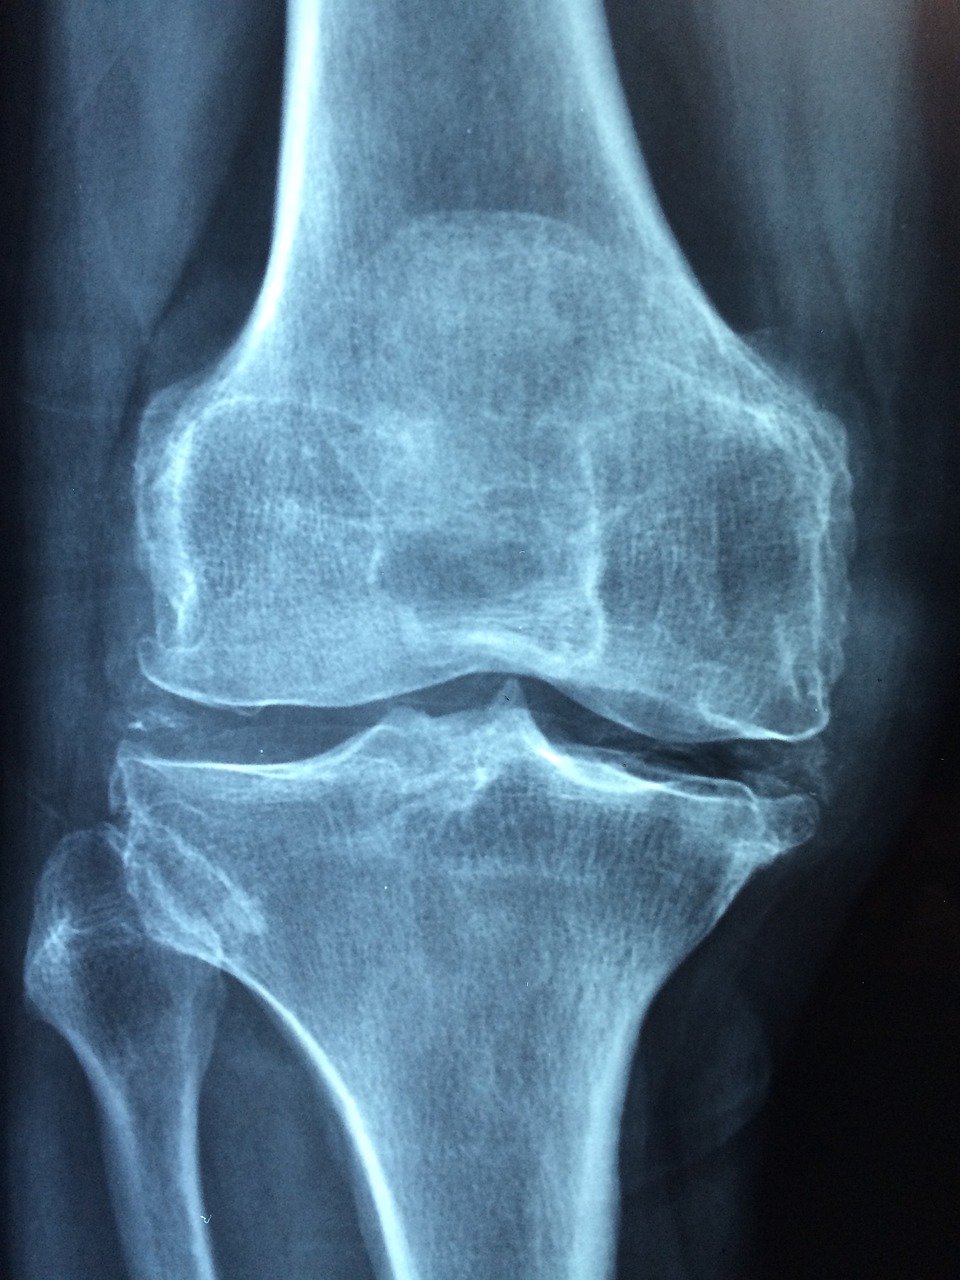

골관절염은 관절 안에서 뼈 끝을 쿠션 시키는 연골이 시간이 지남에 따라 분해되기 시작할 때 발생합니다. 연골이 닳으면서 뼈가 서로 마찰하여 통증, 염증 및 관절 운동 제한을 일으킬 수 있습니다.

영향: 골관절염 증상은 심각도가 다양할 수 있고 무릎, 엉덩이, 손, 척추와 같은 다양한 관절에 영향을 미칠 수 있습니다. 조기 진단과 관리가 질병의 진행을 늦추는데 도움이 될 수 있다는 것을 유의하는 것이 중요합니다.